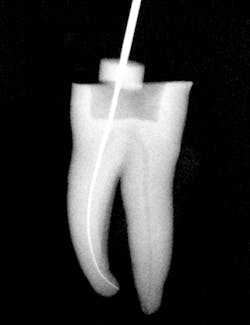

After preparing straight-line access to the canal orifice (figure 1), explore the canal using small-sized instruments. I typically use a size 08 SafeSider by hand with the help of an apex locator to determine working length. I then use the SafeSiders in sizes 10, 15, and 20 to verify patency and confirm a smooth, reproducible glide path (figure 2). I always irrigate and enlarge the glide path to a minimum 20/02 preparation.

Figure 2: Radiograph confirming glide-path creation using SafeSider instruments.